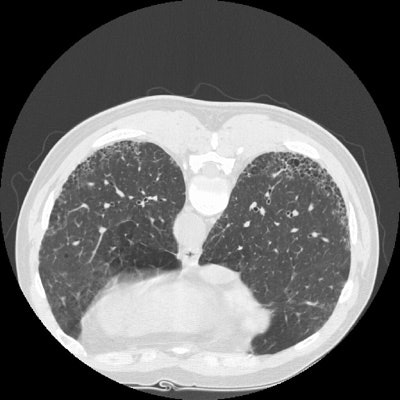

The supine and prone CT images below demonstrate sub-pleural honeycombing within the posterior lower lung zones. The findings are characteristic of UIP. (Click image to enlarge)